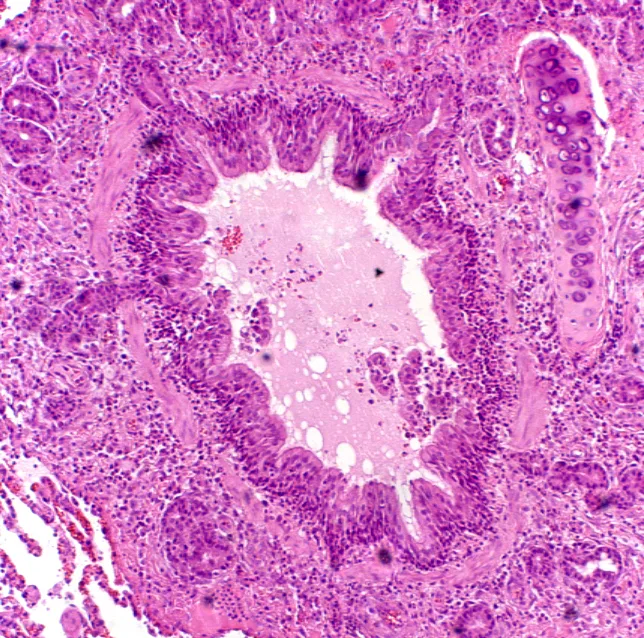

• It is essential to maintain patency of all the ductwork (ie, air passageways from the nares to the smallest bronchiolar ducts) (Figure 2A).

FIGURE 2 A patent airway in a healthy cat (A). An occluded airway from a cat with chronic disease (B). Intraluminal mucus and debris, smooth muscle thickening, numerous inflammatory cells and goblet cells, and subbasement membrane thickening are evident.

• Pathologic changes include airway mucosal changes (epithelial denudation, increased inflammatory cells) and increased goblet cells with intraluminal mucus and inflammatory debris. Substantial subbasement membrane thickening occurs with long-standing disease (ie, airway remodeling) (Figure 2B).